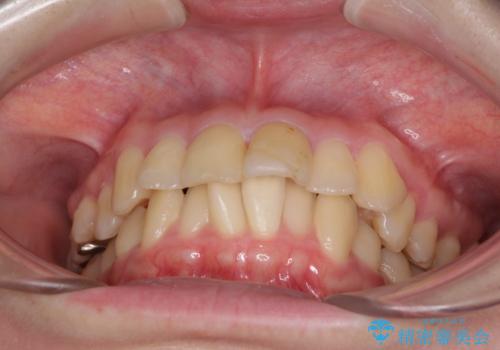

- 前歯の著しい叢生と前突感を気にして来院された患者様です。

叢生が強いため、事前に前歯をワイヤー矯正で速やかに叢生を解消し、その後はインビザラインにて矯正治療を行うこととしました。

ワイヤー矯正を併用したことで前歯の叢生を速やかに解消することができました。

一方口元の突出感を改善するために時間がかかり、2年超を要しましたが、満足のいく仕上がりとなりました。